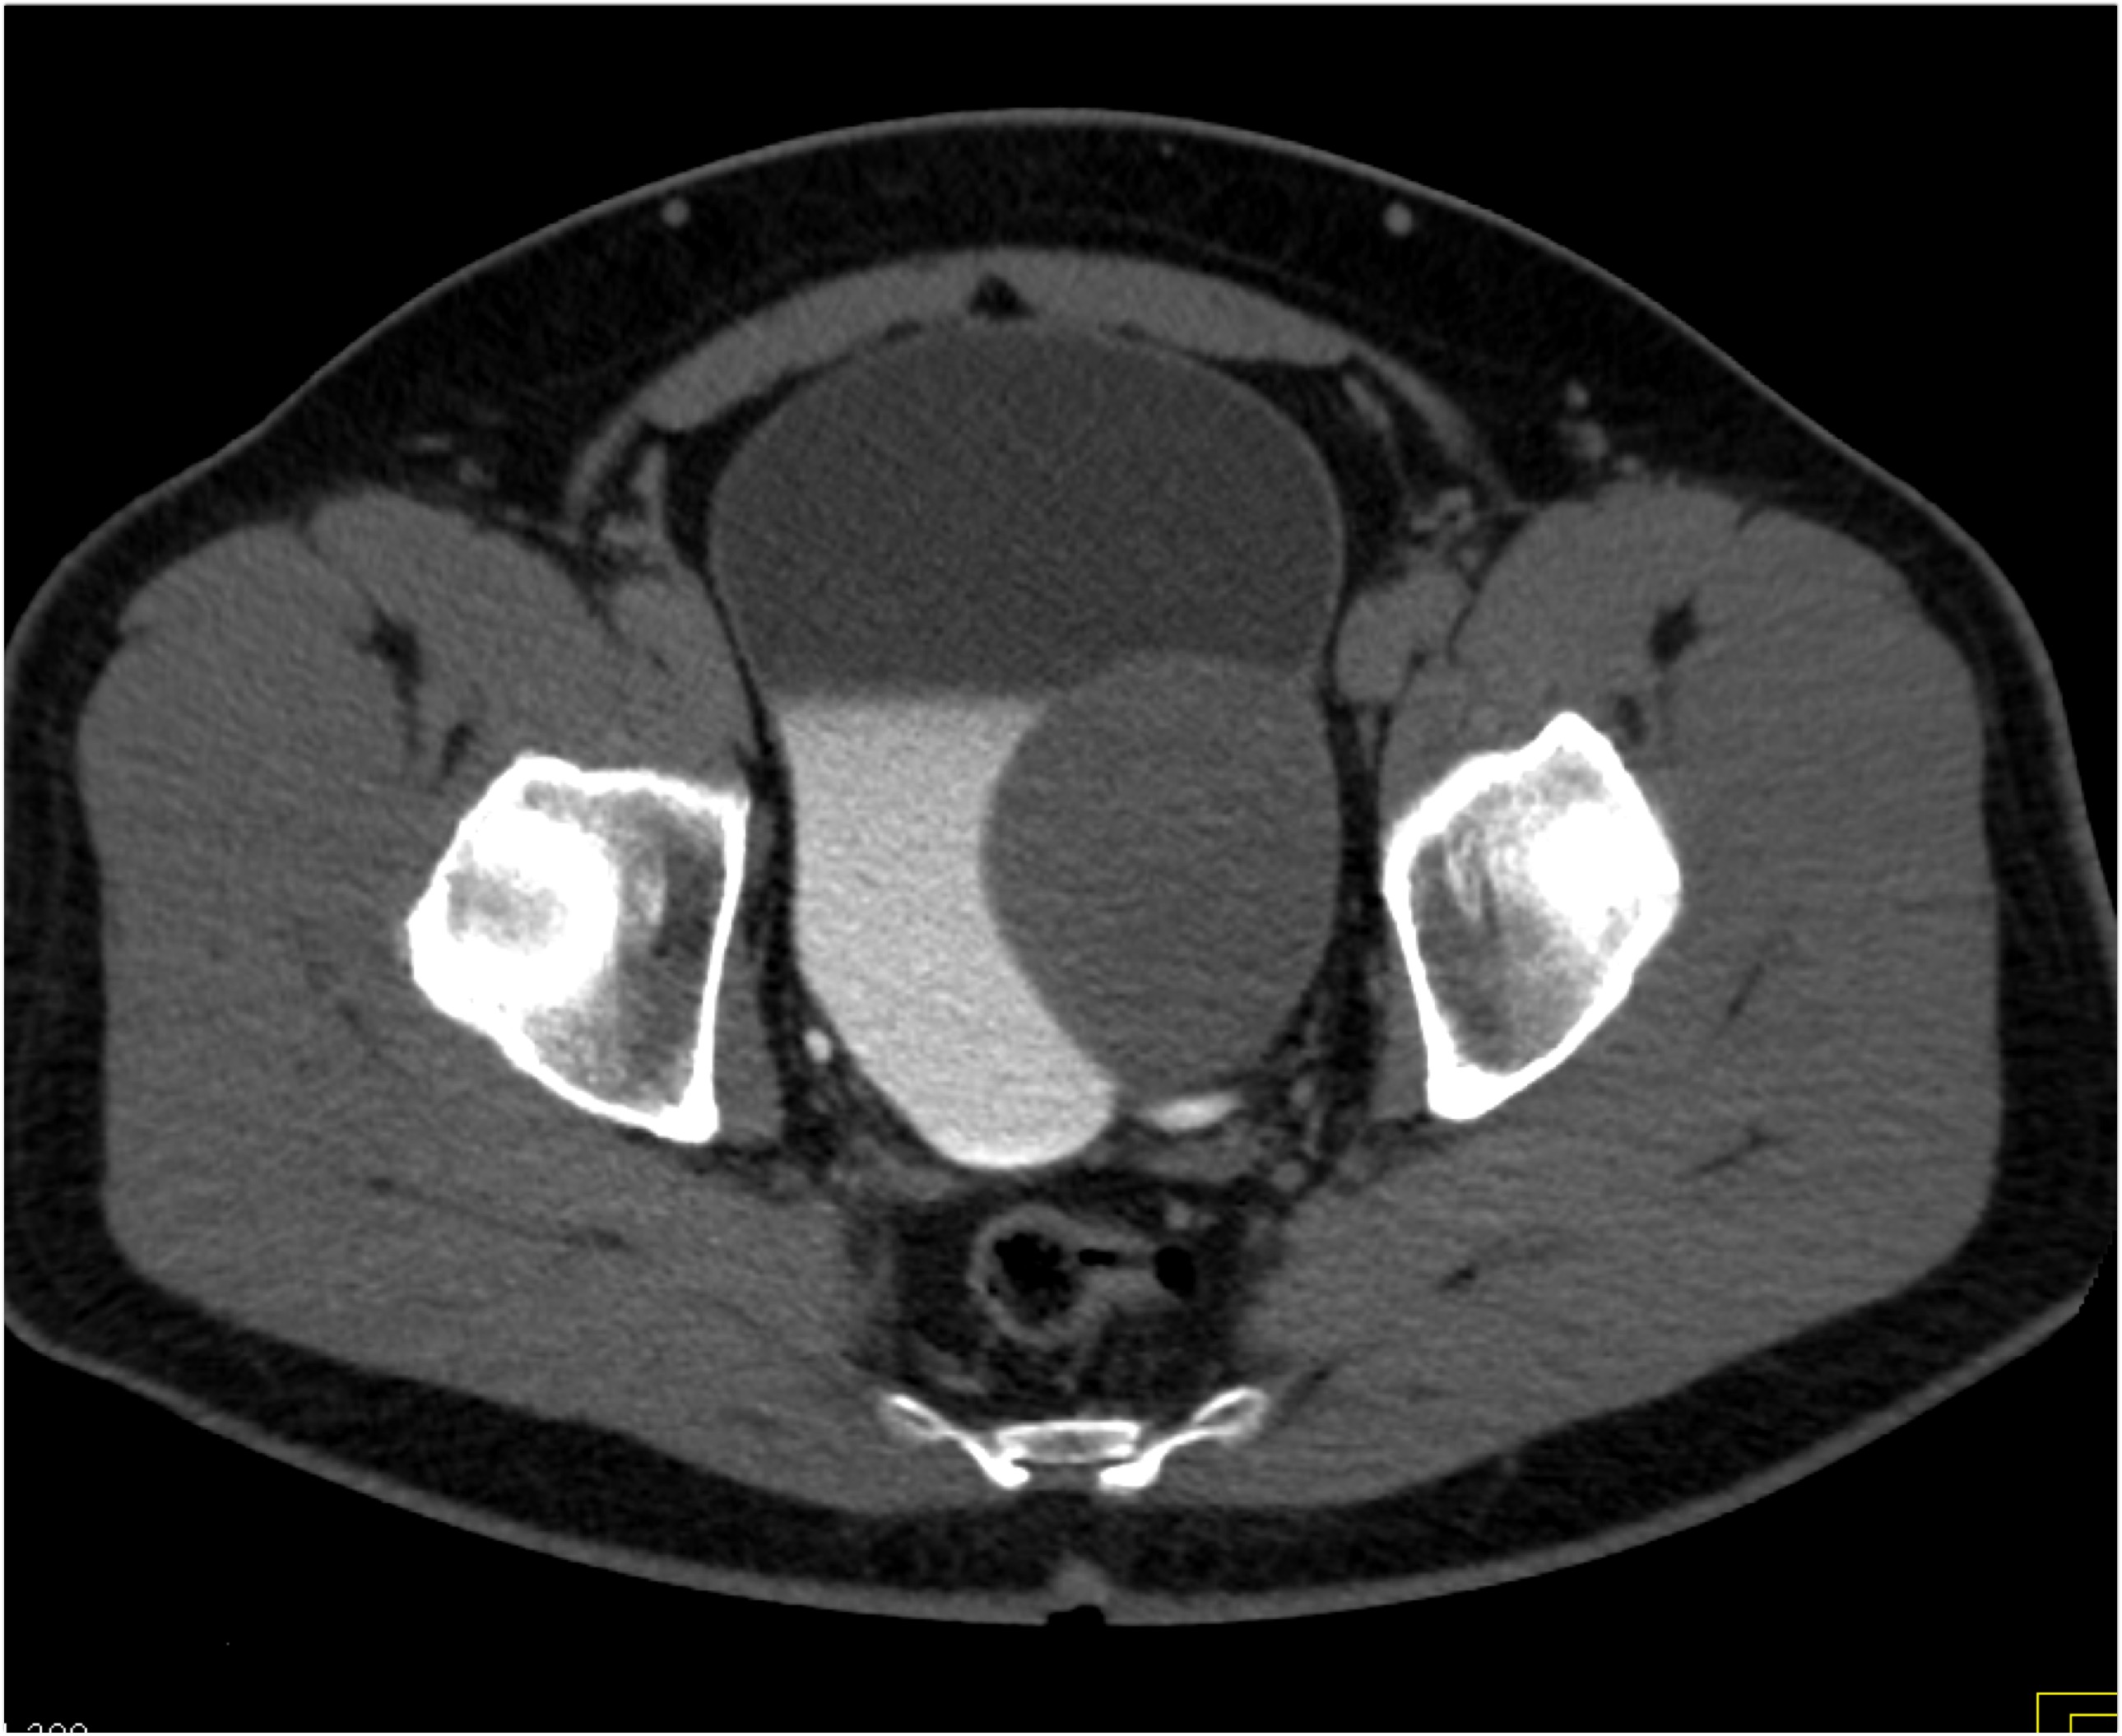

7) In this patient with pelvic pain the best diagnosis is?

lymphoma

silicon injection into buttocks

neurofibromatosis

intramuscular hemorrhage